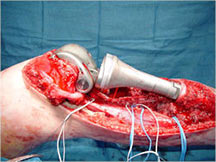

Limb Sparing Surgery

- Surgical principles are the same as those employed for conventional osteosarcoma

- Nowadays, most patients can be treated with a limb sparing resection instead of an amputation

- Prosthetic replacements, cadaver allografts, vascularized bone grafts as well as other methods have been used to reconstruct extremities after tumors are removed